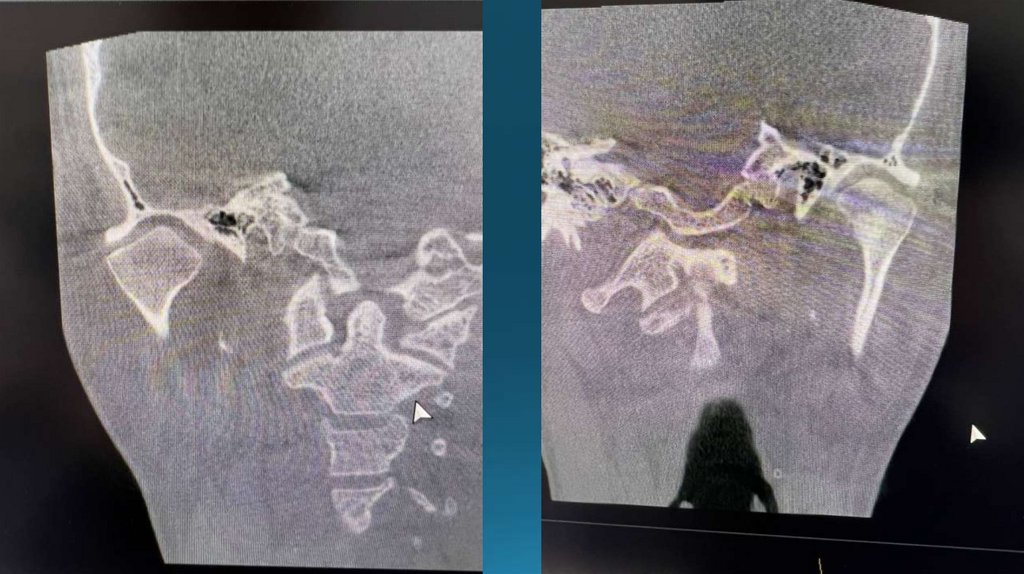

На снимке видим компрессию

биламинарной зоны, что и

приводит к боли